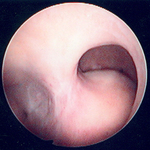

Hysteroscopic examination of the uterine cavity demonstrates the presence of two contiguous submucous uterine fibroids in this patient with persistent heavy menstrual bleeding

From the personal collection of Dr M.F. Mitwally and Dr R.J. Fischer; used with permission